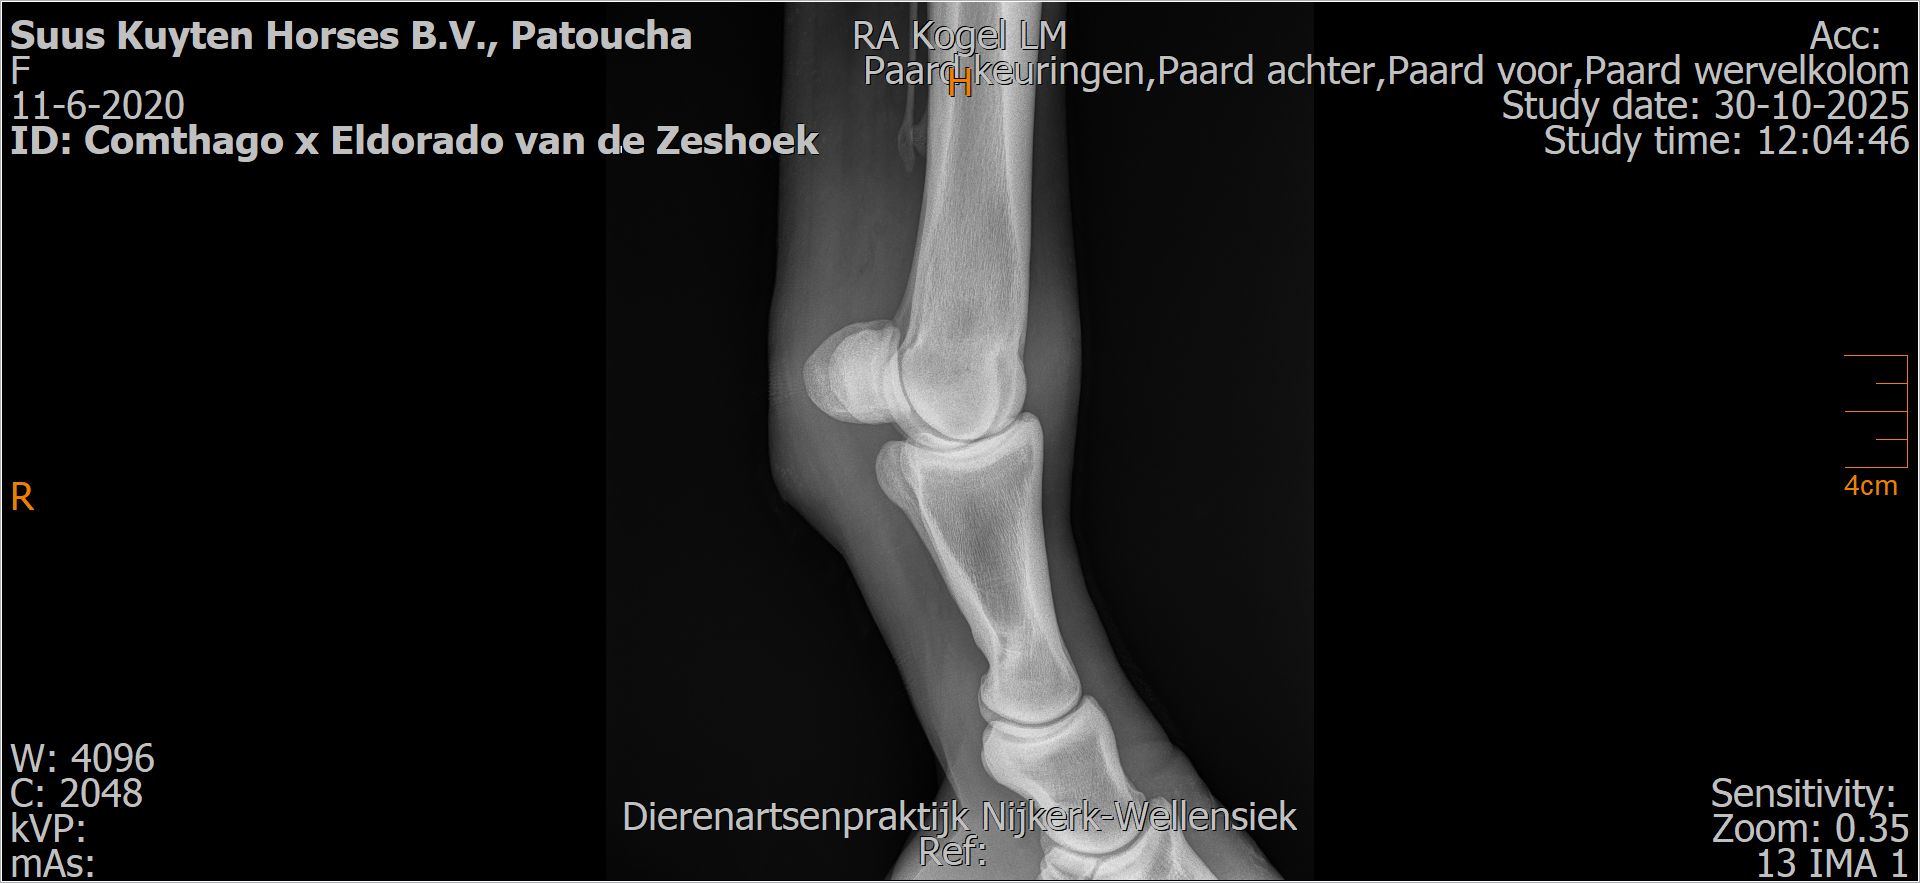

Patoucha

Leeftijd:

7

Röntgenfoto’s